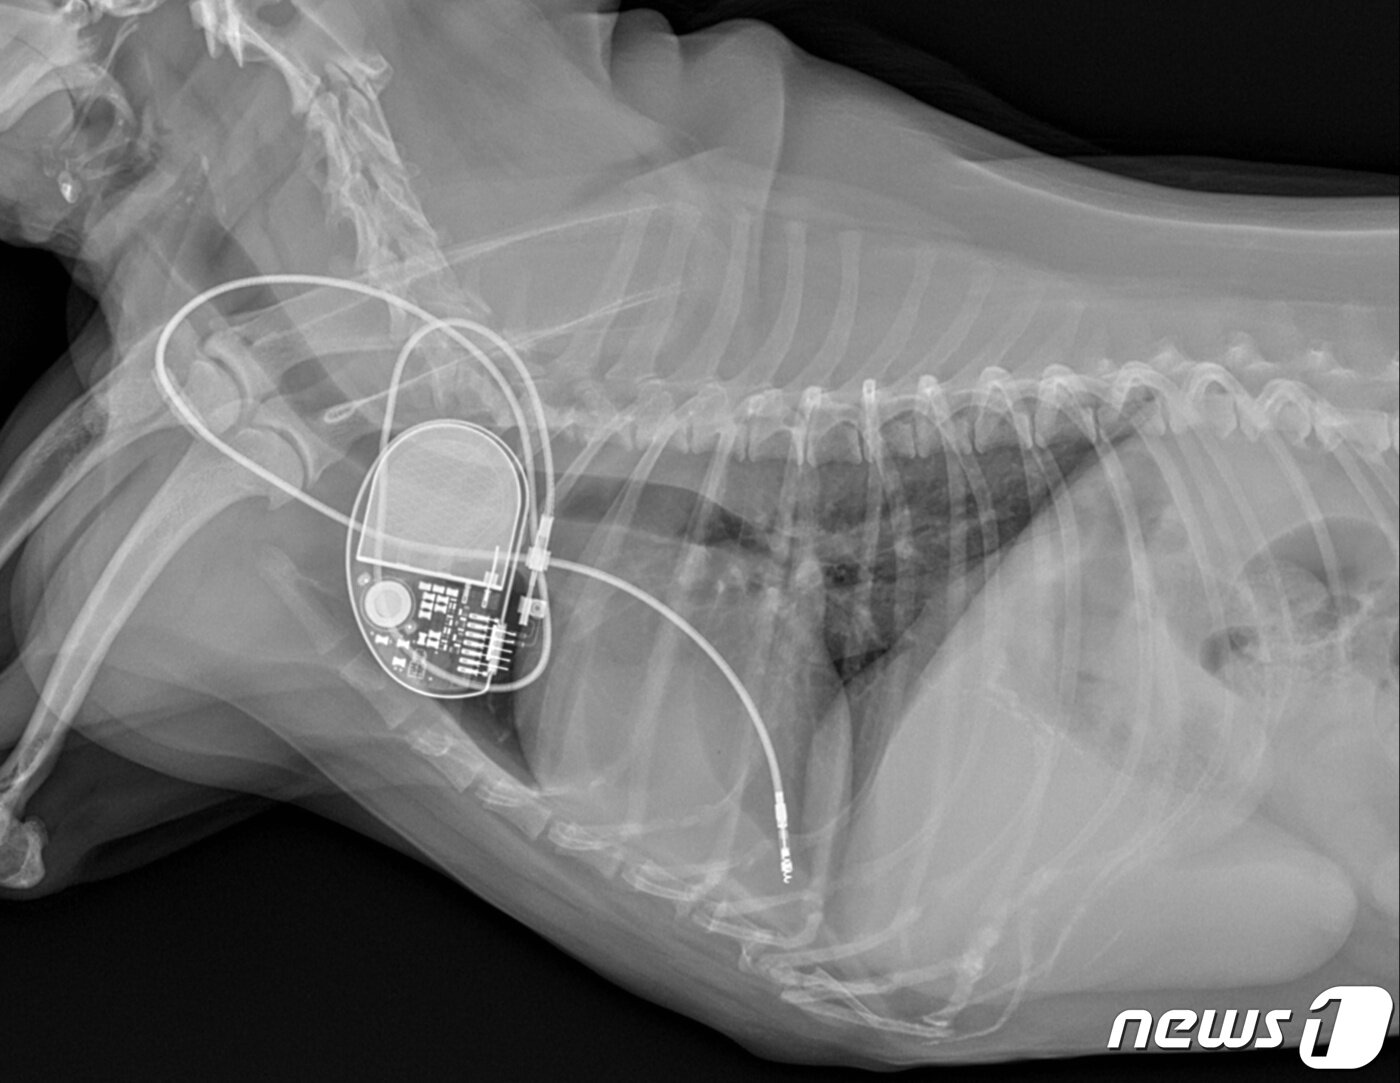

본문 이미지 - 심장 검사를 받고 있는 강아지 신체 모습(VIP동물의료센터 제공) ⓒ 뉴스1

심장 검사를 받고 있는 강아지 신체 모습(VIP동물의료센터 제공) ⓒ 뉴스1